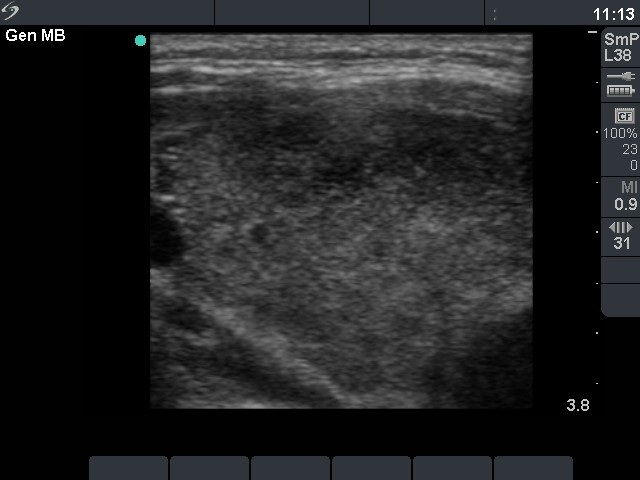

Right lobe, horizontal view

Right lobe, transverse scan. The ventral part of the thyroid is hypoechogenic.